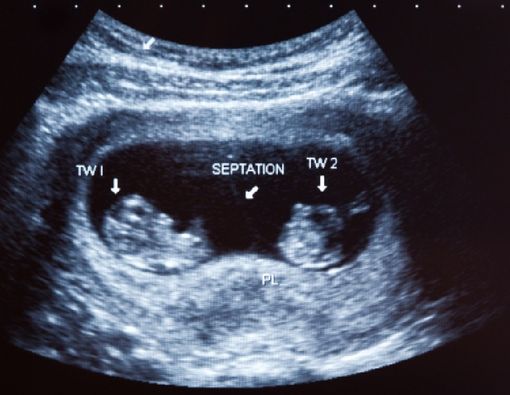

Tidak ada satu orang pun yang mengharapkan hamil kembar siam. Pasalnya, keadaan ini tergolong sebagai kondisi abnormal, di mana dua bayi kembar menempel satu sama lainnya.

Menurut dr. Sara Elise Wijono, MRes, hingga saat ini faktor penyebab hamil kembar siam masih belum diketahui pasti.

“Biasanya, kondisi ini bermula dari 1 telur yang dibuahi, lalu berpisah menjadi 2 janin. Namun, proses pemisahan tersebut tidak terjadi secara sempurna sehingga menyebabkan ada bagian-bagian yang menempel,” jelas dr. Sara.